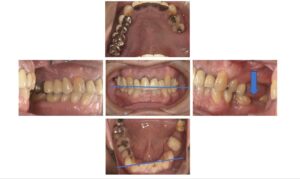

左下を放置していたことにより、左上45が伸びだしてきてしまい、左下がりの咬合平面になっています。また下前歯から左側にかけて態癖によるものと思われる歯の傾斜もあります。

そのせいか右側の臼歯部が悪化してきていて、右上の大臼歯は抜歯になりました。